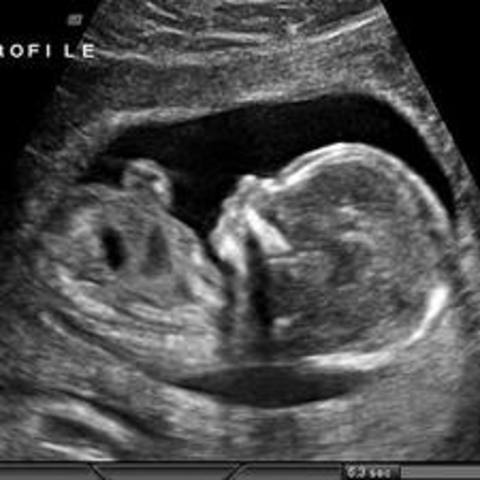

• Week 16

Week 16

The fetus is around 14 cm in length. Eyelashes and eyebrows have appeared, and the tongue has tastebuds

• Week 20

Week 20

The fetus is around 21 cm in length. The ears are fully functioning and can hear muffled sounds from the outside world. The fingertips have prints.